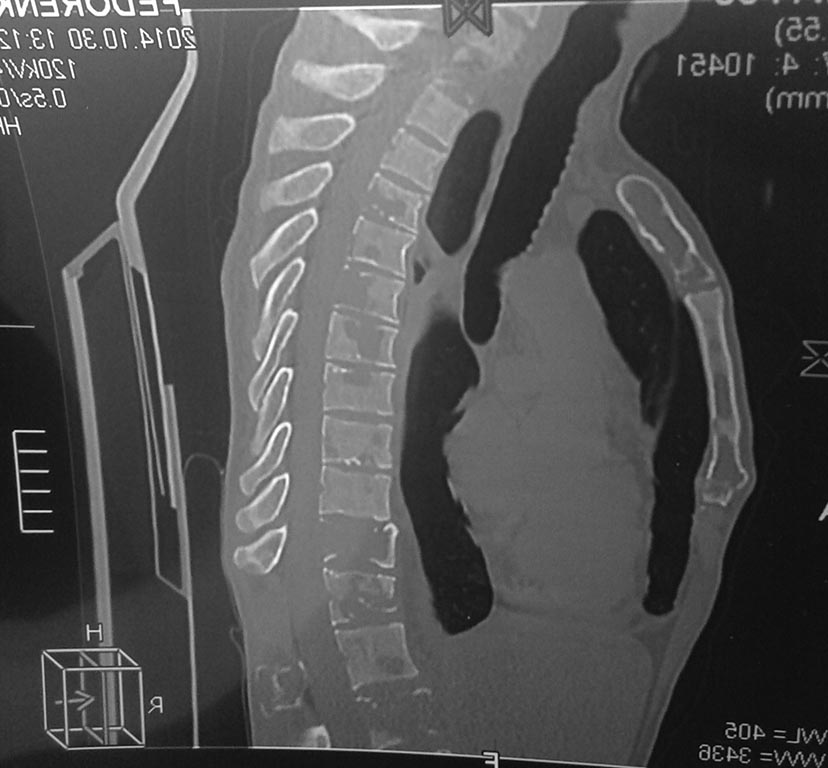

Здравствуйте,Уважаемые коллеги! Пациент М.39лет, работает на разрезе в Якутии. Первый раз обратился по поводу перелома шейки бедренной

(высокоэнергетическая травма-падение с высоты около 4-х метров на работе) кости год назад - прооперирован-закратая репозиция, остеосинтез 3 винтами. Послеоперационный период без осложнений. Уехал домой-на контрольных снимках-срослось-пациент доволен результатом-трудоспособен.

Неделю назад со мной связалась его супруга-резкое , практически молниеносное ухудшение общего состояния, перестал передвигаться, похудел на 15 кг. Жалобы только на боли в позвоночнике, нога не беспокоит. В анализах-ни к чему не предерешься. В Якутии разводят руками.

Сразу извиняюсь на скудность и качество снимка - но это , что они смогли мне переслать. Вопрос - миеломная ли это болезнь, и куда направить его с данной патологией-чтоб поближе к месту его жительства. Спасибо.